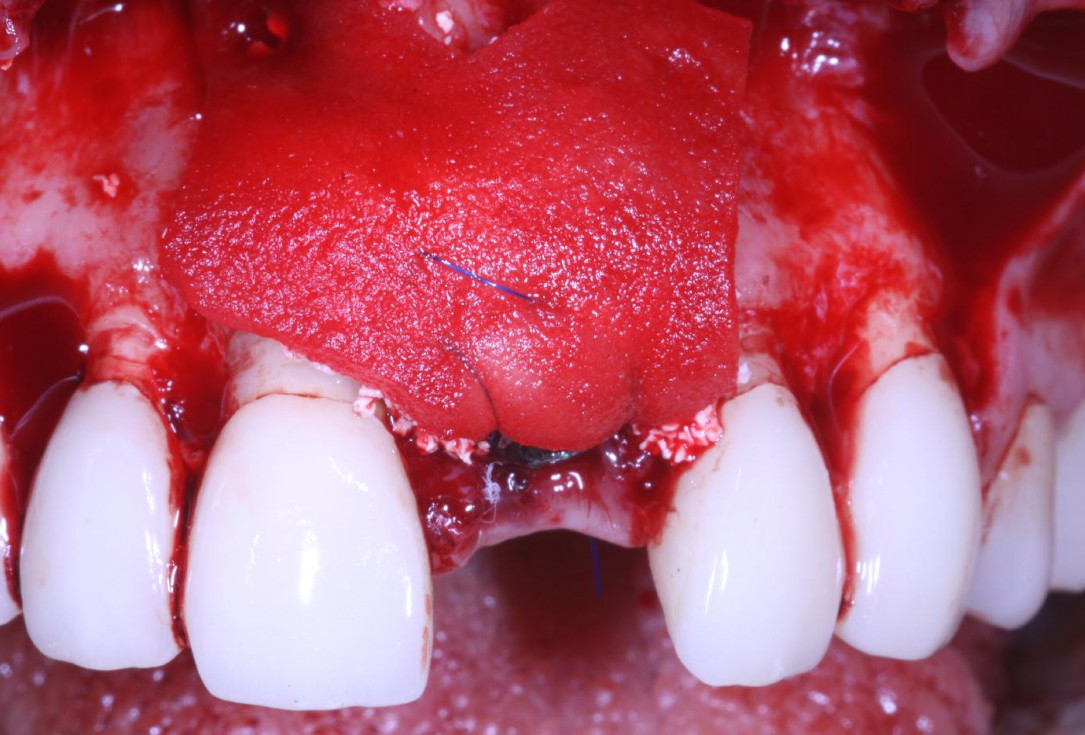

Full-thickness flap preparation bucally and lingually